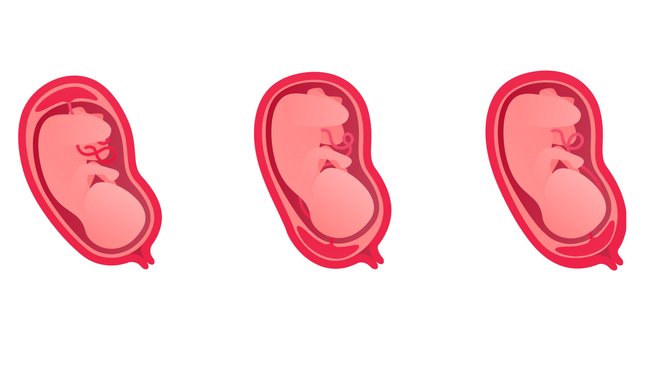

Welche Arten von Plazenta praevia gibt es?

Der lateinische Begriff Placenta praevia heißt übersetzt vorliegende Plazenta und beschreibt ihre Lage vor dem Muttermund, also im unteren Bereich der Gebärmutter. Dabei verschließt sie diesen selten komplett, häufig liegt sie nur über einem Teilbereich. Je nach Höhe und Lage der Plazenta wird zwischen den Folgen Arten unterschieden:

- Placenta praevia totalis: Der innere Muttermund ist durch eine breite Schicht Plazenta-Gewebe komplett verdeckt.

- Placenta praevia partialis: Die Plazenta bedeckt den Muttermund nur teilweise.

- Placenta praevia marginalis: Die Plazenta liegt nahe am Rand des Muttermundes.